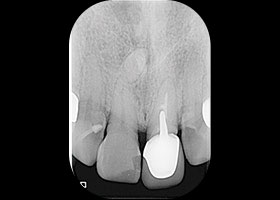

治療前全口X光片、口內正面照片。

假牙拆除前的X光片,可看出假牙已不密合。